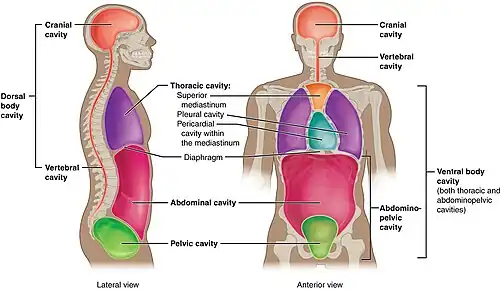

Organs, structured collections of cells with a specific function,[11] mostly sit within the body, with the exception of skin. Examples include the heart, lungs and liver. Many organs reside within cavities within the body. These cavities include the abdomen (which contains the stomach, for example) and pleura, which contains the lungs.

The body consists of a number of body cavities, separated areas which house different organ systems. The brain and central nervous system reside in an area protected from the rest of the body by the blood brain barrier. The lungs sit in the pleural cavity. The intestines, liver, and spleen sit in the abdominal cavity.